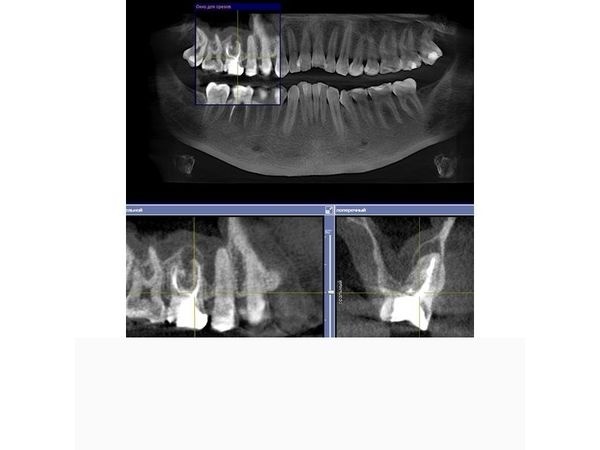

КЛКТ челюстно-лицевой области выявила очаг хронического воспаления в области верхушки мезиального (левого) корня зуба 1.6, второй мезио-букальный корневой канал (второй канал слева, ближе к щеке) был не запломбирован (пропущен).

В области мезиального корня зуба 4.6 отмечался обширный очаг разрушения кости, который распространялся от верхушки корней до места их соединения, тень пломбировочного материала в мезиальных корневых каналах нечёткая и неоднородная, располагалась пристеночно, доходила до половины и второй трети каналов (мезиального и дистального).